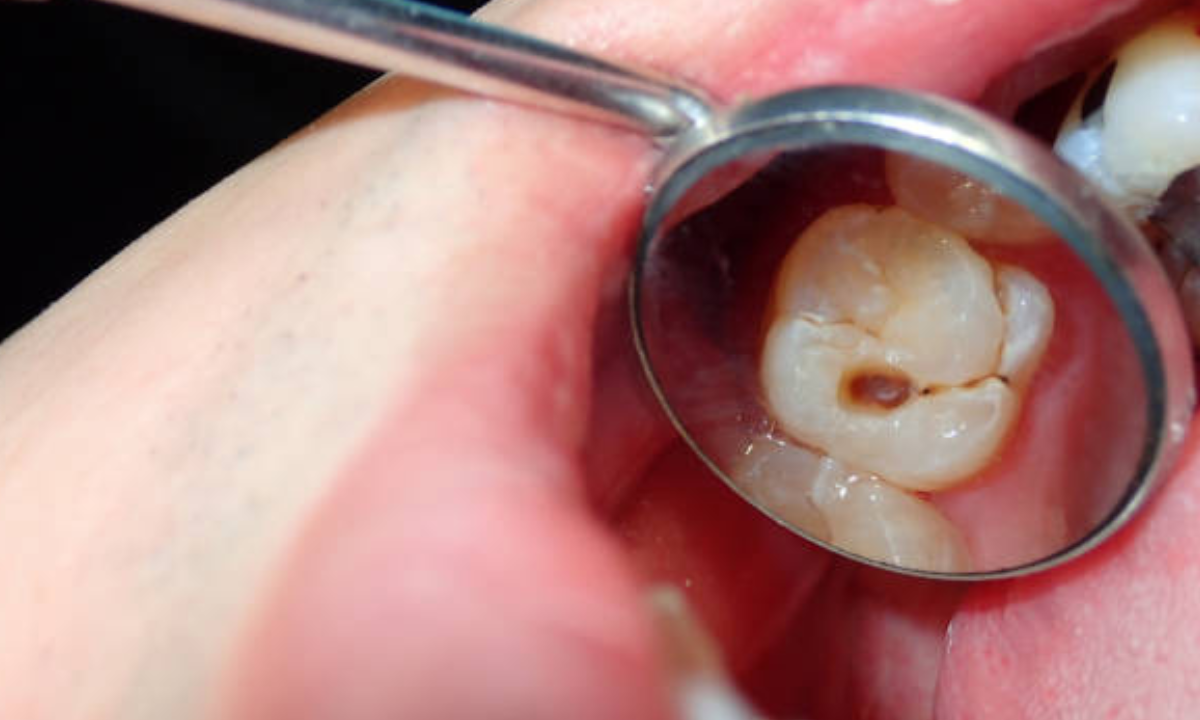

Tooth Decay (Cavities)

The most prevalent oral disease in children is tooth decay. Bacterial activity creates an acid residue known as plaque, a sticky layer accumulating sugars from food on dental surfaces. These acids erode the tooth enamel slowly over time, producing cavities.

Fluoride treatment: Fluoride is applied to assist in the re-mineralizing of dental enamel and can even reverse early stages of tooth decay.

Dental Fillings: For mildly larger cavities, a pediatric dentist will make fillings to restructure the tooth and prevent it from getting worse.